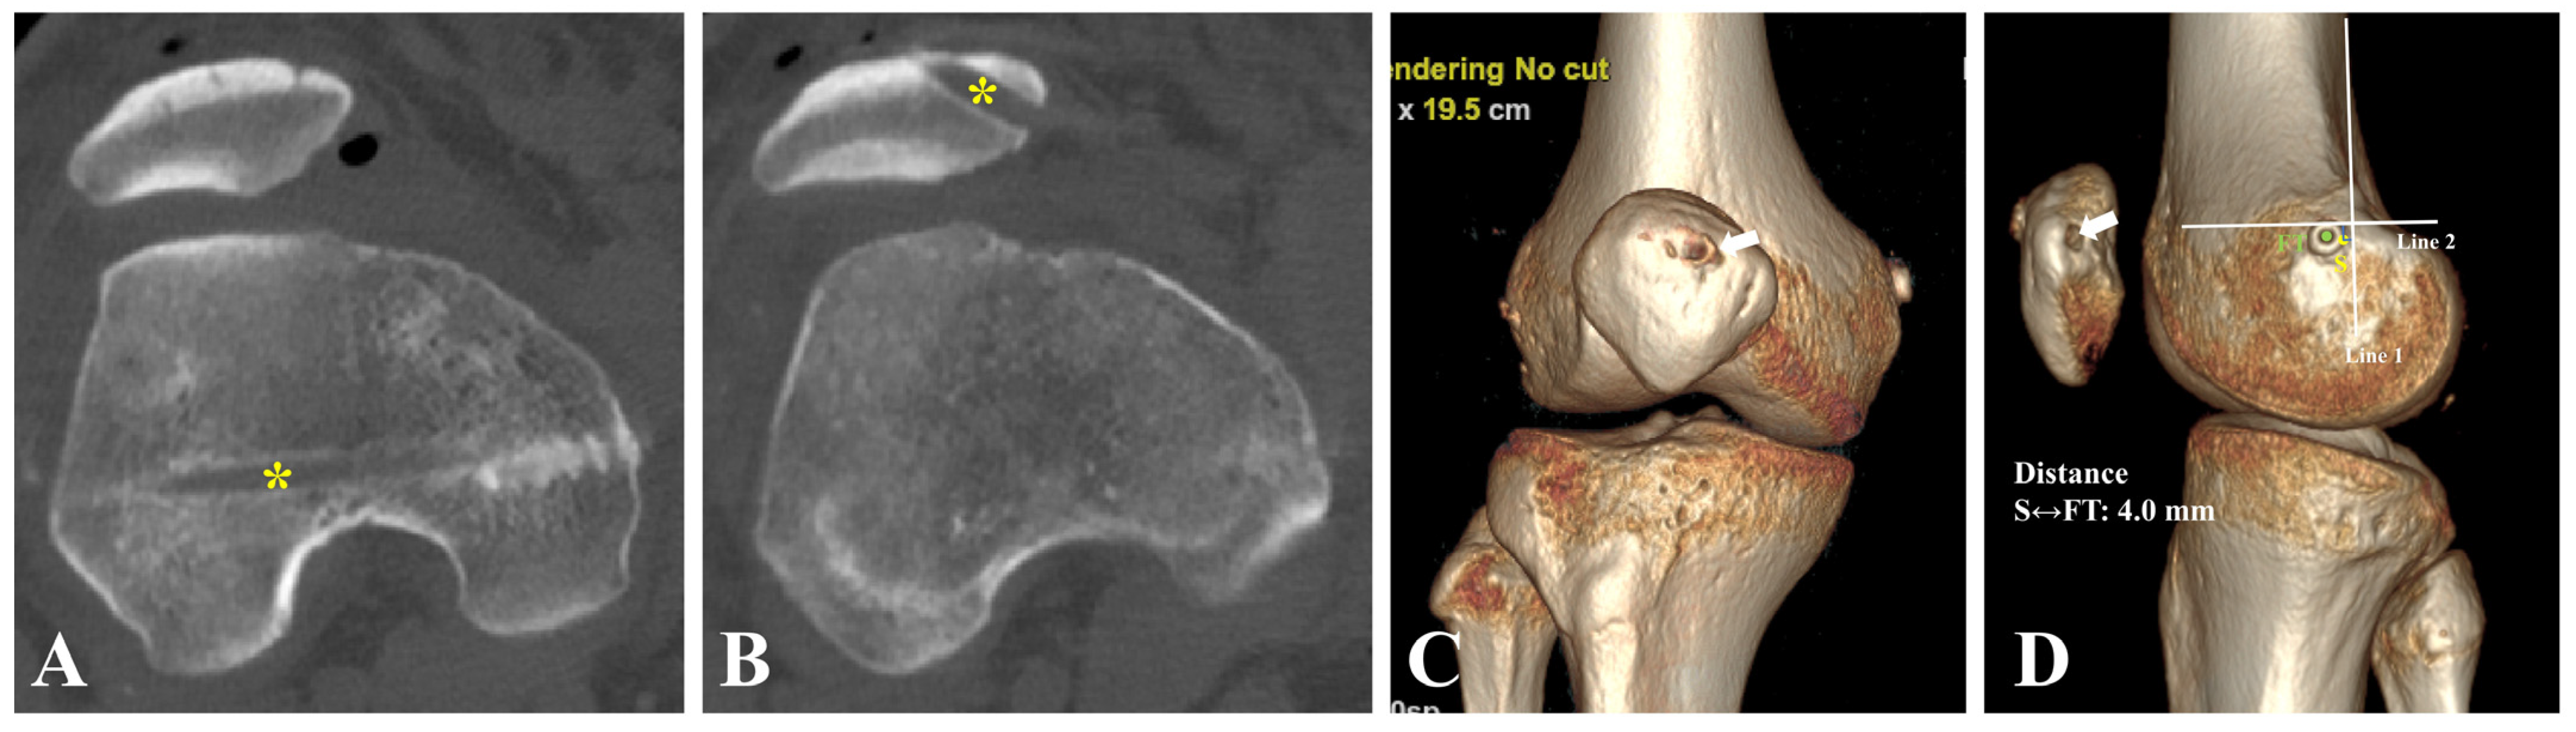

2.5. Positioning of Femoral Tunnel